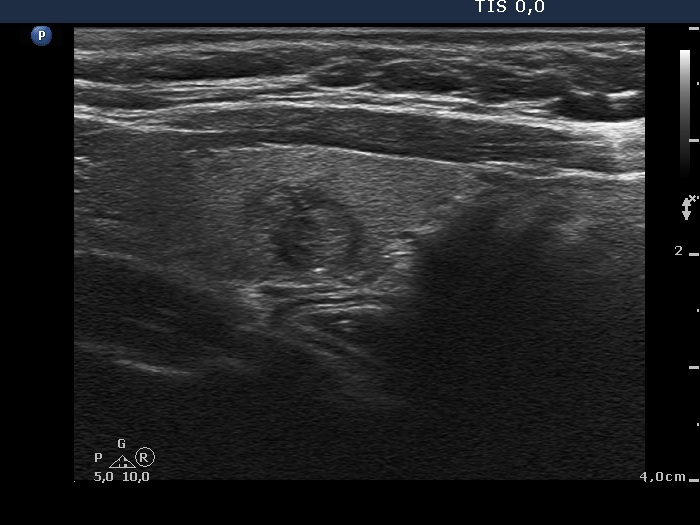

The composition of the nodule - case 1473 (ultrasonographic picture 7)

Right lobe, longitudinal scan

Left lobe, longitudinal view. The minimally hypoechogenic lesion presents halo sign.